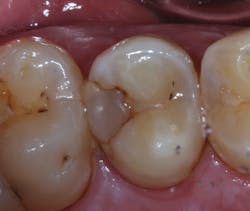

When a carious lesion and the Class II cavity preparation extend near to or apical to the cementoenamel junction, the sandwich technique can be used. The technique is described as a layering of various restorative materials within the cavity preparation. It involves placing RMGI at the base of the cavity preparation, followed by curing and the addition of composite restoratives to complete the restoration. If the remaining layers of composite resin completely encase the RMGI, it is considered a "closed" sandwich technique. If the RMGI is exposed to the oral environment at the base of the restoration, it is considered an "open" sandwich technique (figures 1a and 1b).

Figures 1a and 1b: RMGI sandwich techniques

This technique is not new and was originally proposed by Suzuki and Jordan. (4) According to Liebenberg, "The open-sandwich technique allows the least amount of microleakage of the various direct restorative options currently available." (5,6) This occurs because traditional composite bonding at the cavosurface and interproximal sites often have a complex combination of substrates that include enamel and varying levels of dentin, depending on the depth of the lesion. Liebenberg continues, "For dentin bonding, it appears far easier to achieve a seal than to maintain it, and in vivo studies have confirmed that resin-dentin bonds degrade in the oral cavity." (5,7)